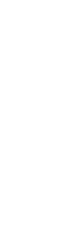

Improving Wound Healing and Infection Control in Long-term Care with Bacterial Fluorescence Imaging

Kelso, MR et al. Adv Skin & Wound Care 2024

Integrating Point-of-Care Bacterial Fluorescence Imaging-Guided Care with Continued Wound Measurement for Enhanced Wound Area Reduction Monitoring

Derwin, R. et al. Diagnostics 2024